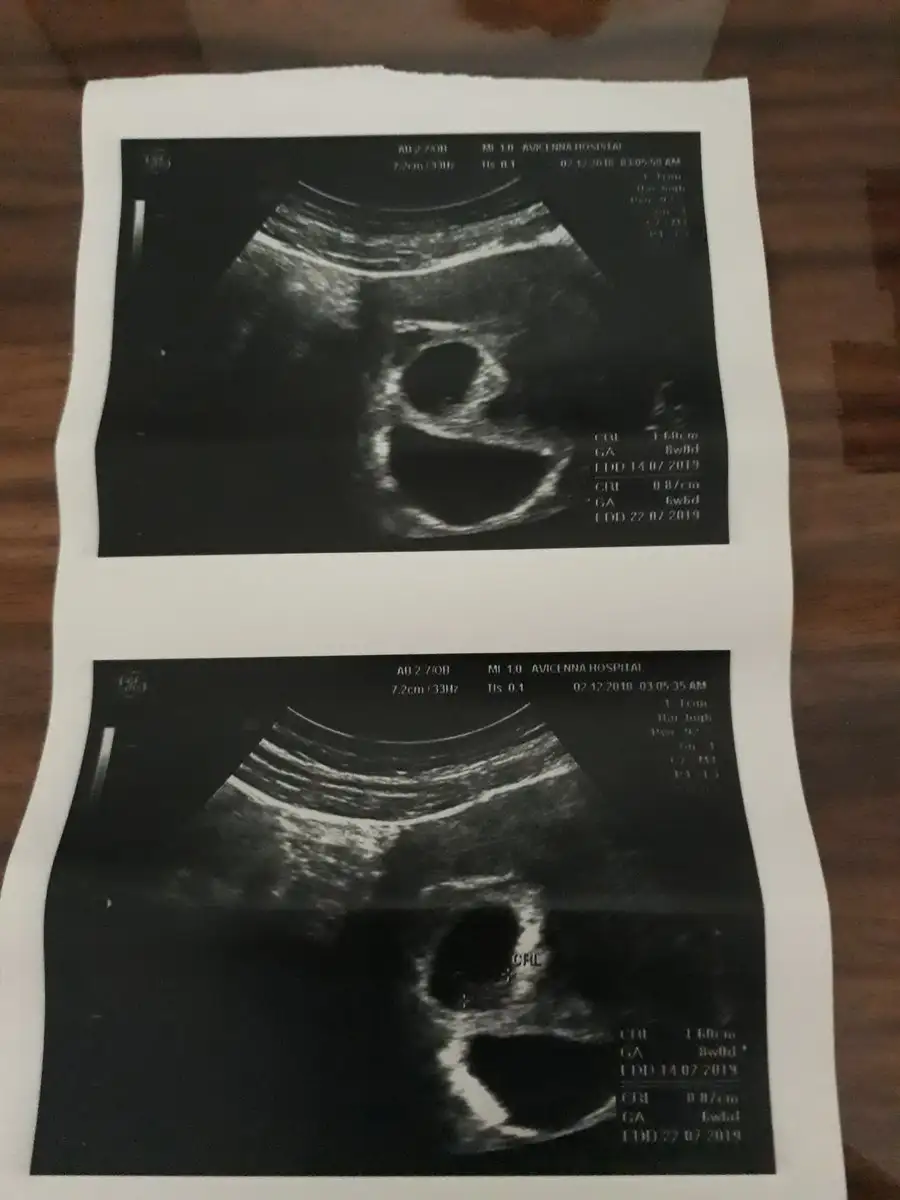

Aaaaa çok şaşırdımmmm şuannnn 6 haftalıkkem nasıl görmemiş doktorun kuzum yaa evet tarifsiz bi duygu zararı varmı bilmem ama gayet son ses dinledik 15 aralıkta diğer randevum inşallah sağlıkla devam eder bebişlerimiz canımmKizlar size bi mujde vericem benimkiler ikizmissasirdik dun ogrendik. Babamlar ctesi calisiyor die acilde bi doktora gtti gorsnler die heves ettiler doktor ben iki goruyorm dedi ikisnnde kalbi atiyoms biri 7 hafta biri 8 hfta gorunuyo minik olan saklanms:) kendi doktoruma gidicem haftaya inss riskli bisi yoktur birinin kesesi kucuk cnku